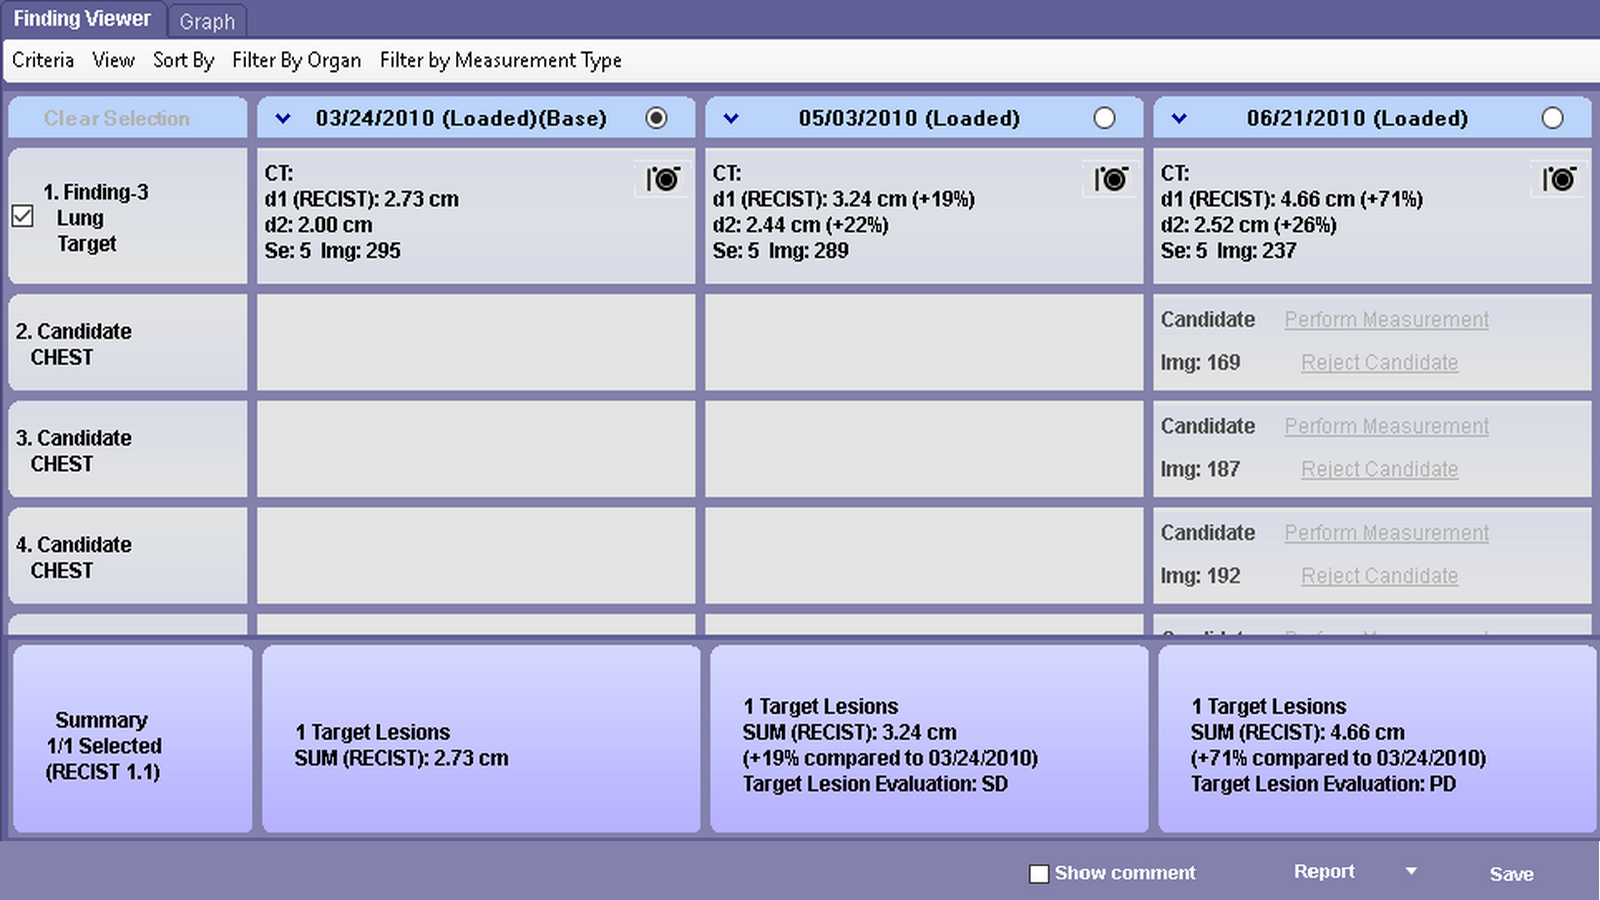

MT Lung workflow is a comprehensive lung analysis tool used to segment, analyze and track lung lesions over the course of time. SphereFinder allows a second look as the software helps identify spherical areas of interest. The Findings Viewer aids in tracking, classifying and measuring confirmed areas of interest. The Measurement Tracking feature tracks confirmed measurements over time.

MT Lung workflow is a comprehensive lung analysis tool used to segment, analyze and track lung lesions over the course of time. SphereFinder allows a second look as the software helps identify spherical areas of interest. The Findings Viewer aids in tracking, classifying and measuring confirmed areas of interest. The Measurement Tracking feature tracks confirmed measurements over time.

Supporta criteri come LRADS®1/01 Le misurazioni e le classificazioni vengono visualizzate su Findings Viewer.

Criteri di monitoraggio come LRADS®1/01

Visualizzazione dei grafici del visualizzatore dei risultati in base ai criteri scelti.